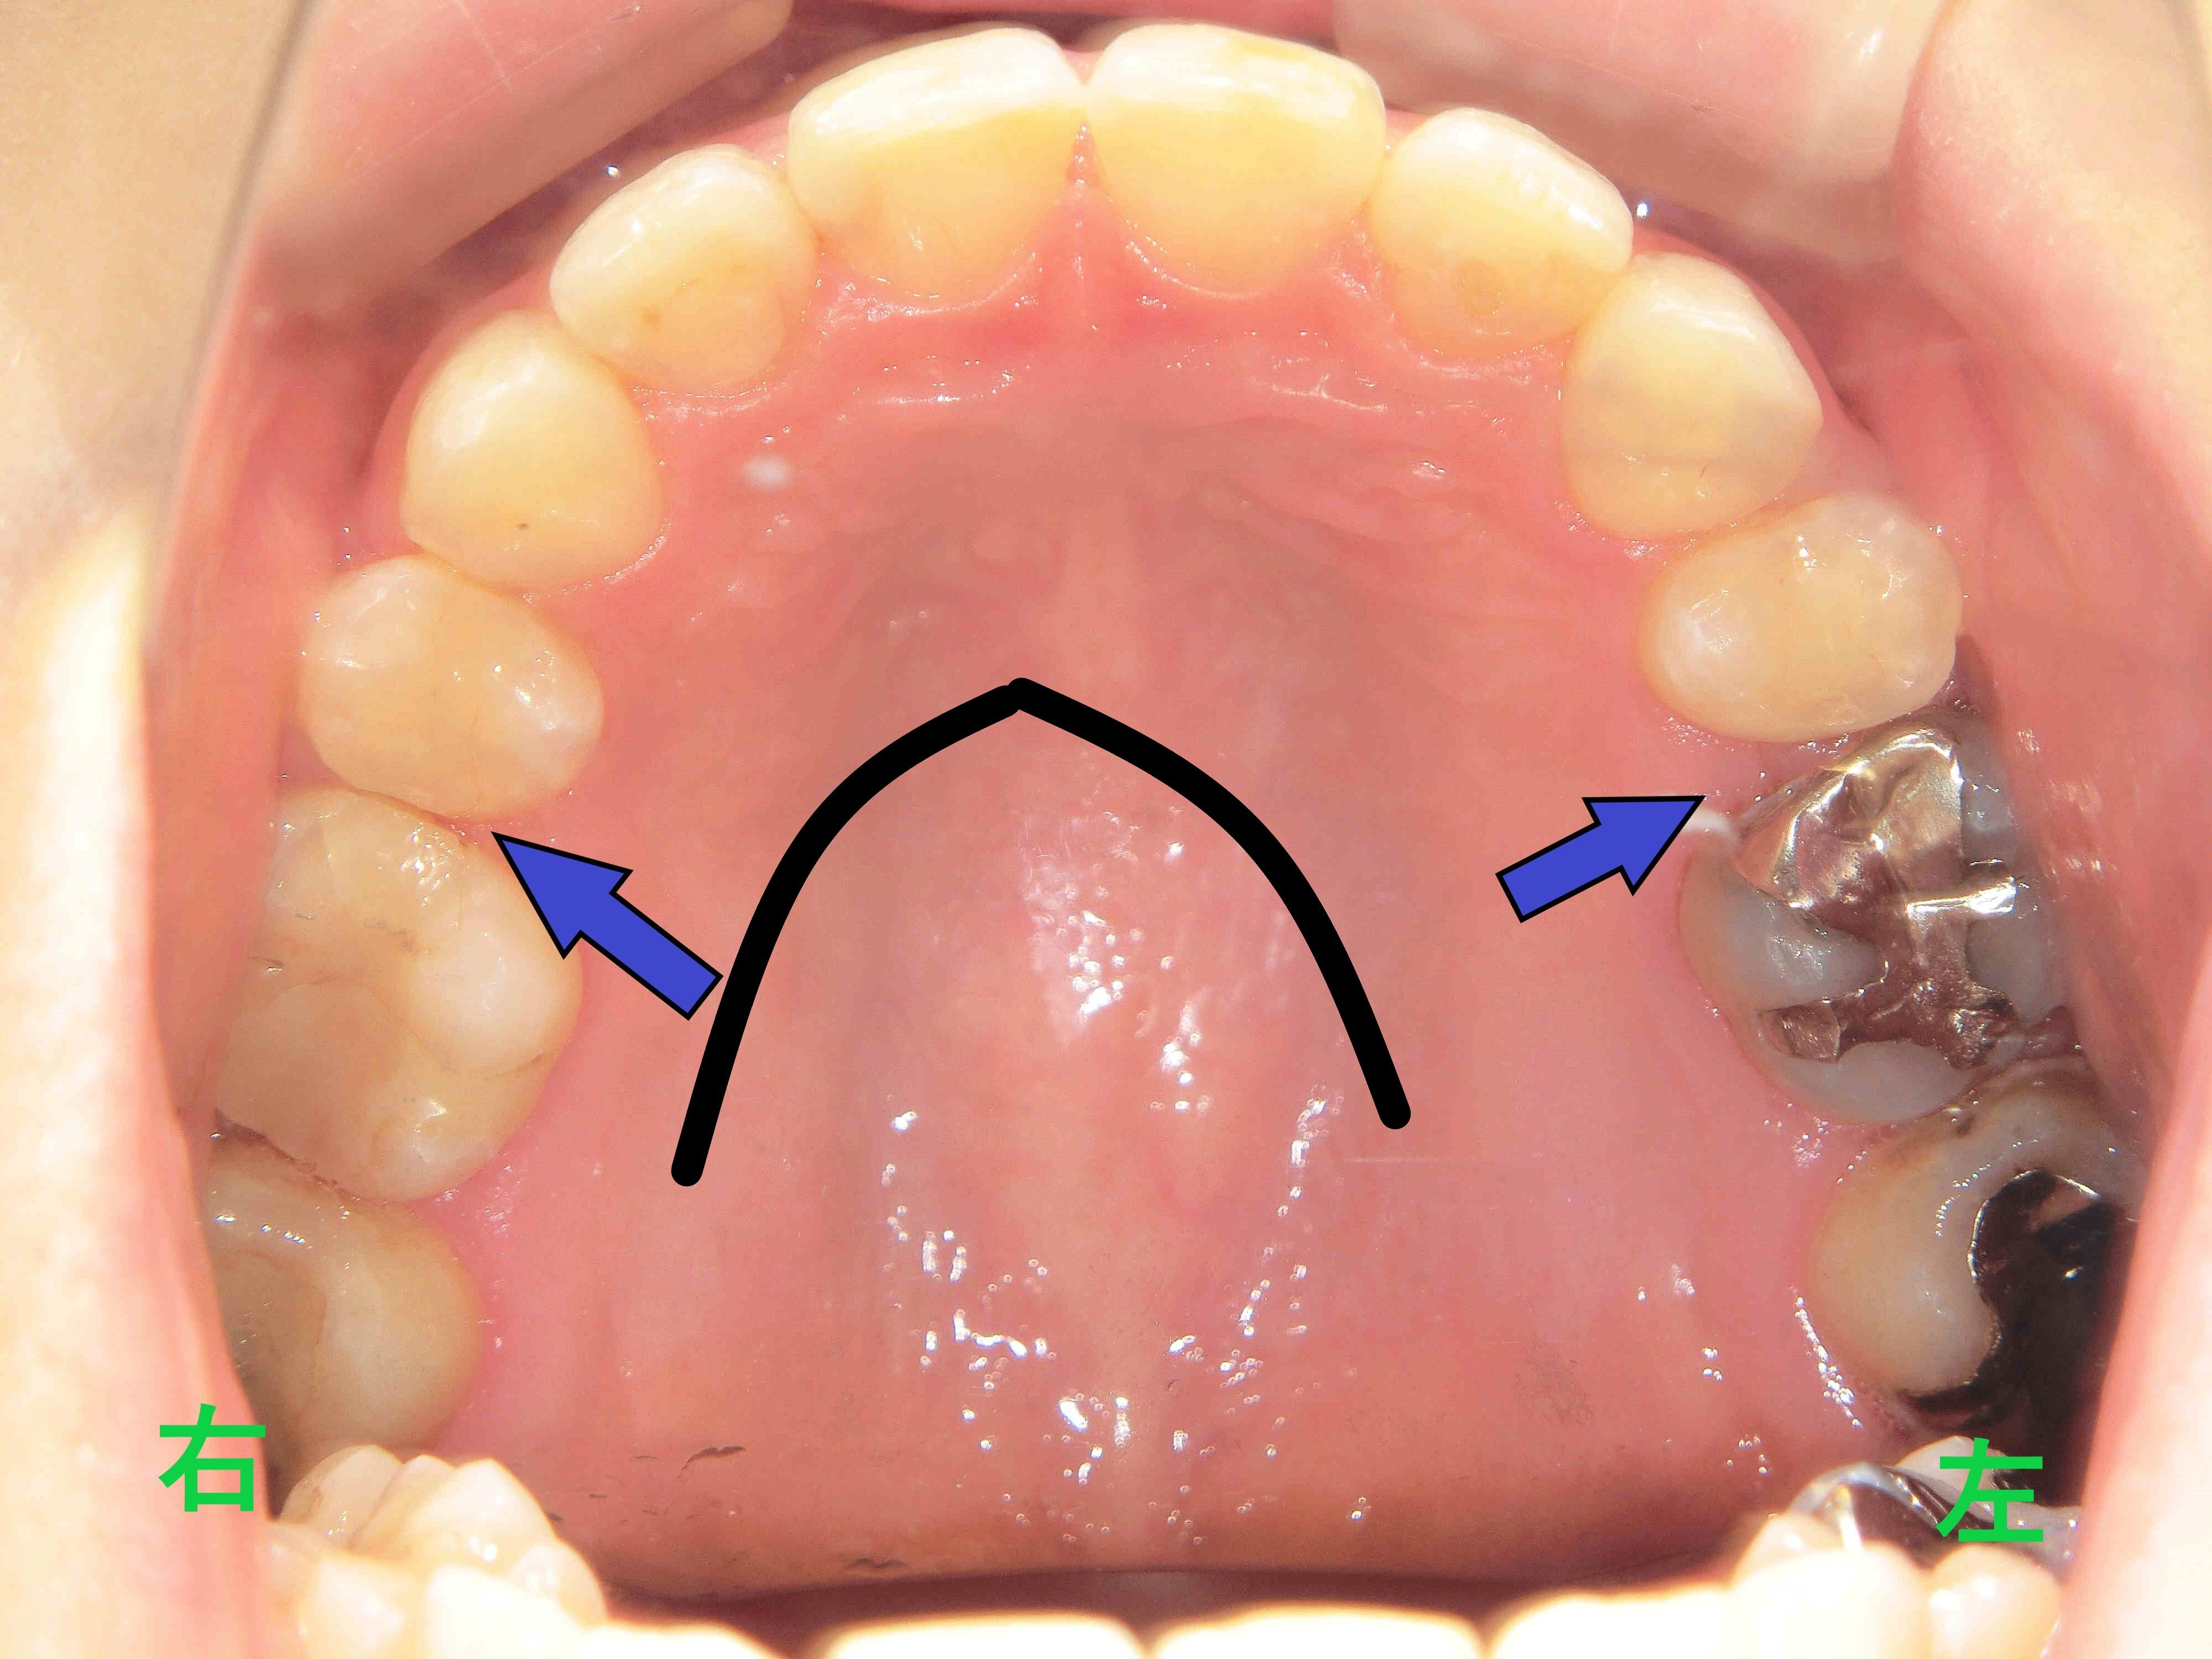

治療前と治療後の口腔内写真を比較すると、上顎前歯が後方へ移動し、下顎前歯との接触が確認できます。また、治療前はV字型であった歯列が、治療後はU字型に改善されています。

当院の矯正治療は、歯列を左右に拡大しながら前歯を後方に移動させる方法を採用しており、口腔内容積の減少を抑えるよう配慮しています。このような配列は、舌の位置や気道への影響、歯ぎしり・食いしばりの軽減にも寄与すると考えられています。

さらに、歯列拡大は審美的観点からも重要です。前歯が後方へ下がりすぎると、唇の支えが減少し、老けた印象を与える場合があります。当院では、機能性と審美性を両立した治療を心がけております。